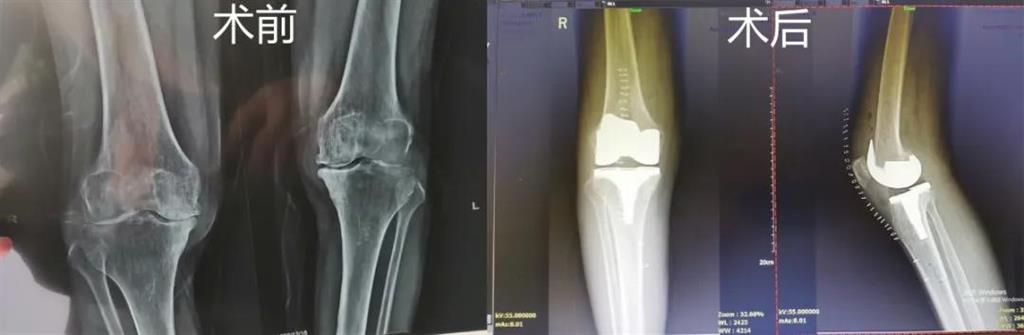

突破!和平國際醫(yī)院成功完成一例計(jì)算機(jī)導(dǎo)航膝關(guān)節(jié)置換術(shù)

最近,和平國際醫(yī)院骨科中心開展了一項(xiàng)新業(yè)務(wù)——計(jì)算機(jī)導(dǎo)航膝關(guān)節(jié)置換術(shù),而年邁78歲的李奶奶則幸運(yùn)地成為該手術(shù)的首個受益者。這也是溫州地區(qū)率先將骨科傳統(tǒng)手術(shù)與計(jì)算機(jī)導(dǎo)航系統(tǒng)相結(jié)合應(yīng)用的成功案例,也是和平國際醫(yī)院骨科中心在膝關(guān)節(jié)置換術(shù)方面所取得的一次重大突破!

李奶奶已經(jīng)被兩側(cè)膝關(guān)節(jié)疼痛困擾了5年左右時間,尤其是右側(cè)膝關(guān)節(jié),近一年來癥狀明顯加重,無法正常生活。經(jīng)過多方打聽,一家人來到和平國際醫(yī)院。

和平國際醫(yī)院副院長、骨科中心主任劉丹在診斷后發(fā)現(xiàn),老人雙側(cè)膝關(guān)節(jié)患有骨性關(guān)節(jié)炎,右側(cè)膝關(guān)節(jié)較為嚴(yán)重,而且關(guān)節(jié)磨損嚴(yán)重,關(guān)節(jié)間隙基本消失。

經(jīng)過進(jìn)一步檢查后,劉丹帶領(lǐng)團(tuán)隊(duì)在計(jì)算機(jī)導(dǎo)航系統(tǒng)的輔助下,為老人實(shí)施了右側(cè)全膝關(guān)節(jié)置換手術(shù)。術(shù)中出血明顯減少,術(shù)后疼痛腫脹等反應(yīng)輕微,畸形矯正力線恢復(fù)理想,而且功能恢復(fù)快速,術(shù)后四天就可以下地行走。

據(jù)劉丹主任介紹,計(jì)算機(jī)導(dǎo)航膝關(guān)節(jié)置換術(shù)可以避免打開股骨髓腔,從而明顯減小手術(shù)創(chuàng)傷,減少術(shù)中出血,能夠更精準(zhǔn)地從三維角度調(diào)整手術(shù)截骨方向,恢復(fù)肢體對線,并能進(jìn)行精確的軟組織平衡,從而使患者獲得良好的術(shù)后功能恢復(fù)。